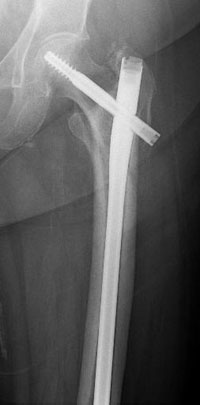

The intramedullary nail is placed directly into the marrow canal of the bone through an opening made at the top of the greater trochanter. A lag screw is then placed through the nail and up into the neck and head of the hip. As with the compression hip screw, sliding of the lag screw and impaction of the fracture take place.

Repair of an intertrochanteric fracture with an intramedullary nail. The nail is in the hollow cavity of the femur (thighbone) rather than on the side of it (as with a plate).

Repair of subtrochanteric fracture with a long intramedullary nail.

Interlocking screws at the end of the nail make the fixation more secure.